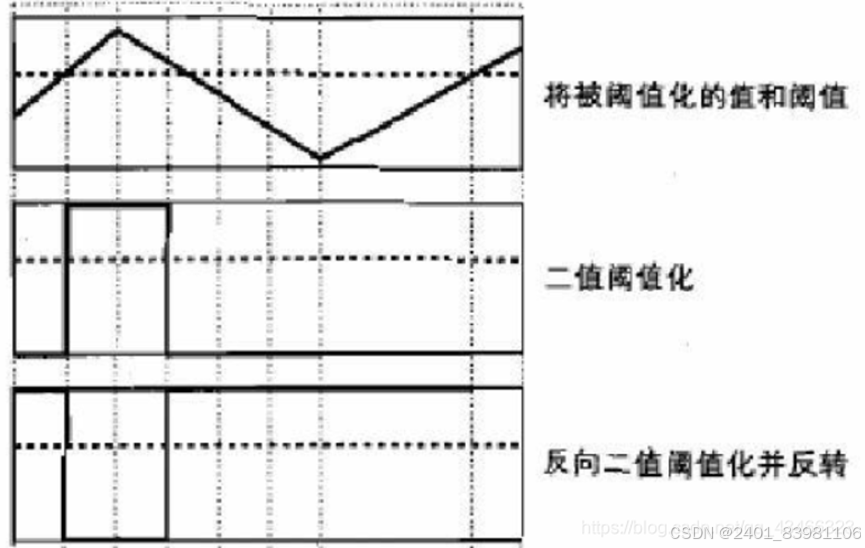

- 阈值分割:根据像素灰度值选取合适阈值进行分割。

(阈值法主要利用舌象与背景颜色的差异,通过设置阈值对图像的像素点进行分类,从而实现舌头的定位与分割。其优点是算法实现简单,计算效率高,但是该算法对图像的要求较高,鲁棒性差。)

采用动态阈值分割算法提取舌体初始轮廓,采用舌体校正模型得到最终舌体。数据证明,该提取方法得到的图像在抗噪性和准确性方面具有优越性,在舌体凹凸区域也具有良好的分割效果。(反2进制阈值化分割)